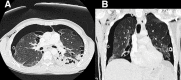

Simultaneous bilateral pneumothorax in an immunocompromised HIV patient with Pneumocystis jirovecii pneumonia

Pneumocystis in humans is caused by a unicellular and eukaryotic organism called P. jirovecii. The overall incidence of P. jirovecii pneumonia (PCP) has decreased with the use of highly active antiretroviral therapy and the use of chemoprophylaxis with trimethroprim sulfametoxazole (TMP/SMX) in cases of immunosuppressed patients. However, approximately 85% of patients with advanced HIV infections continue to experience this disease with inadequate management. Pneumocystis infection can present with spontaneous pneumothorax in 2-6% of cases [8] which can be a potentially fatal complication. We report the case of a 32-year-old man presented with P. jirovecii pneumonia who developed cystic lesions and spontaneous bilateral pneumothorax in spite of TMP/SMX treatment. We consider it an interesting clinical case because few simultaneous bilateral pneumothorax cases have been described directly related to the PCP.